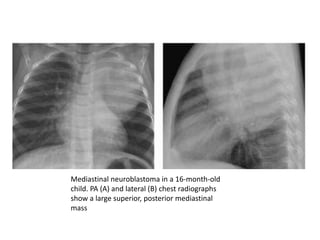

Mediastinal neuroblastoma in a 16-month-old

child. PA (A) and lateral (B) chest radiographs

show a large superior, posterior mediastinal

mass

Mediastinal neuroblastoma ina 16-month-old child. PA (A) and lateral (B) chest radiographs show a large superior, posterior mediastinal mass